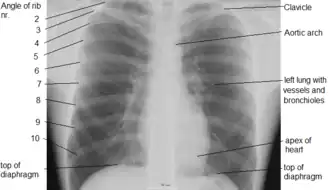

An X-ray of a human chest area, with some structures labeled

The contents of the thorax include the heart and lungs (and the thymus gland); the major and minor pectoral muscles, trapezius muscles, and neck muscle; and internal structures such as the diaphragm, the esophagus, the trachea, and a part of the sternum known as the xiphoid process. Arteries and veins are also contained – (aorta, superior vena cava, inferior vena cava and the pulmonary artery); bones (the shoulder socket containing the upper part of the humerus, the scapula, sternum, thoracic portion of the spine, collarbone, and the rib cage and floating ribs).